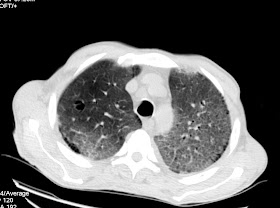

Varón de 63 años en estudio por episodios de hematuria indolora desde hace 3 meses